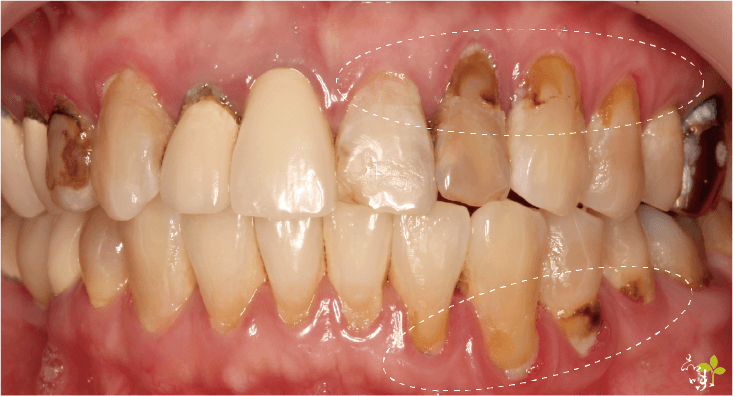

牙周病

牙周病會造成齒槽骨破壞,進而導致牙齦隨齒槽骨消失而後退,這時建議先進行牙周病治療才是上策。

而當牙齒已經出現鬆動或嚴重動搖的情形時,甚至是需要拔牙的情況,針孔微創牙齦手術是無效的。